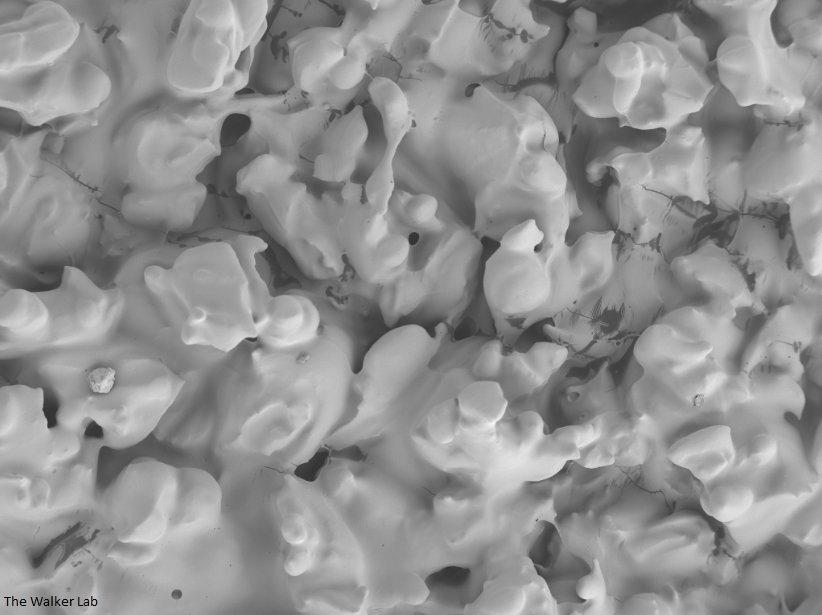

Silicone urinary catheters have smooth surfaces, while latex urinary catheter surfaces are rough. Regardless of the catheter material, deposition of host inflammatory factors alters the surface and facilitates infection by atypical pathogens.

Latex Catheter Surface